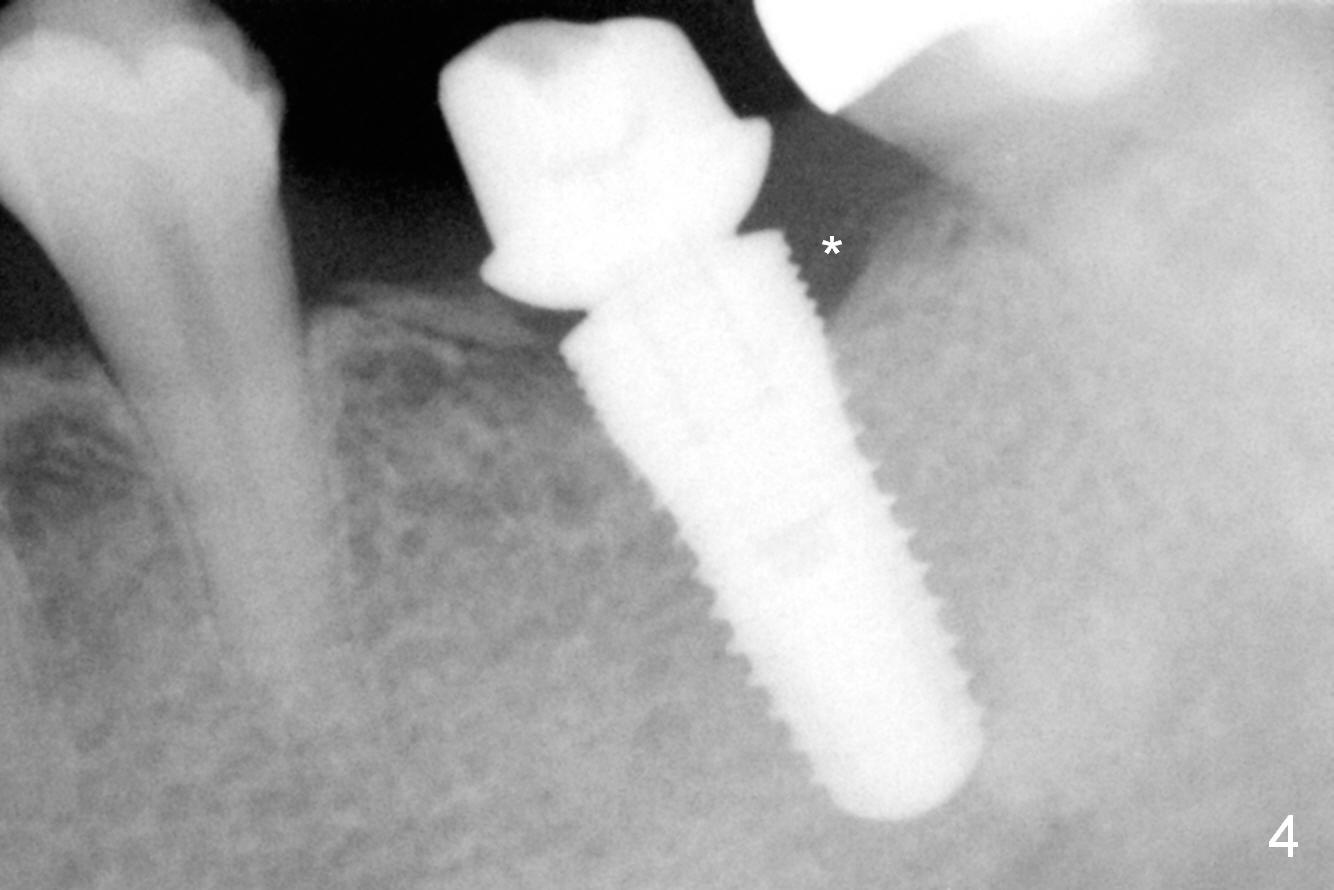

The edentulous ridge at #19 is moderately wide at the base, but pointed at the crest (Fig.1). After raising flaps, it appears that the ridge can hold a 5 mm implant using an implant positioner. The initial osteotomy is 12 mm deep and about 4 mm from the Inferior Alveolar Canal (Fig.2 yellow dashed line). Sequential osteotomy is carried out until 5x12 mm. Because of the pointed crest, 4.5 drill is used to extend the osteotomy at ~ 13 mm so that 12 mm implant can be placed a little deeper to reduce the amount of thread exposure. A 5.3x12 mm implant cannot be seated as deep as expected. A 5.3x10 mm drill with stopper is used before placing the same implant as mentioned above at the desirable depth (Fig.3). The insertion torque is > 60 Ncm. An abutment is placed immediately and an immediate provisional is fabricated and seated. Two to 3 microthreads buccally and lingually are covered by autogenous bone graft and collagen membrane. The patient returns for impression 4 months postop. There is bone loss distally (Fig.4 *). His oral hygiene is excellent. It is hoped that the bone loss will not get worse in the next visit.

It appears that the diameter of the implant should be also controlled. A smaller implant may not lead to thread exposure and ultimately bone loss. It remains to be true 7 months post cementation (Fig.5). It appears that a 4.5 mm implant is better choice. There is no sign of periimplantitis. Oral hygiene, soft and hard tissues remains basically the same 2 years post cementation (Fig.6). The mesial open margin may be related to failure of impression material to get to the margin in spite of laser gingivectomy.